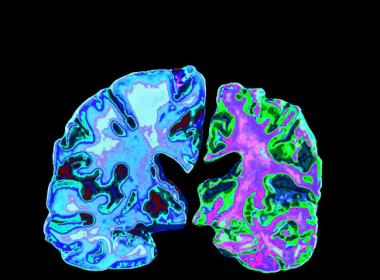

How inattention-hyperactivity affects the brain

A new study published in The Canadian Journal of Psychiatry sheds light on the relationship between brain development and behavioural disorders such as inattention-hyperactivity disorder, a condition similar to Attention Deficit Hyperactivity Disorder (ADHD). “The term inattention-hyperactivity, as defined in this study, refers to a set of behaviours such as fidgeting and[Read More…]